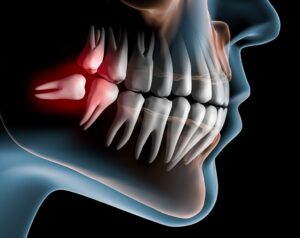

Os terceiros molares são os últimos dentes a nascerem entre 15 e 21 anos. É Bastante comum que não apontem totalmente para fora quando isso acontece o dente fica impactado, torto e retido dentro do osso é o que chamamos dente incluso.

Um dente incluso pode ficar na horizontal (deitado) dentro do maxilar o que contribue para infecção e dificuldade de remoção.

A falta de espaço para o siso nascer no lugar certo atrapalha seu desenvolvimento, nesse caso ele passa a empurrar os outros dentes na tentativa de encaixar na arcada causando cáries nas raízes dos dentes vizinhos desalinhamentos e infecções como a pericoronarite.